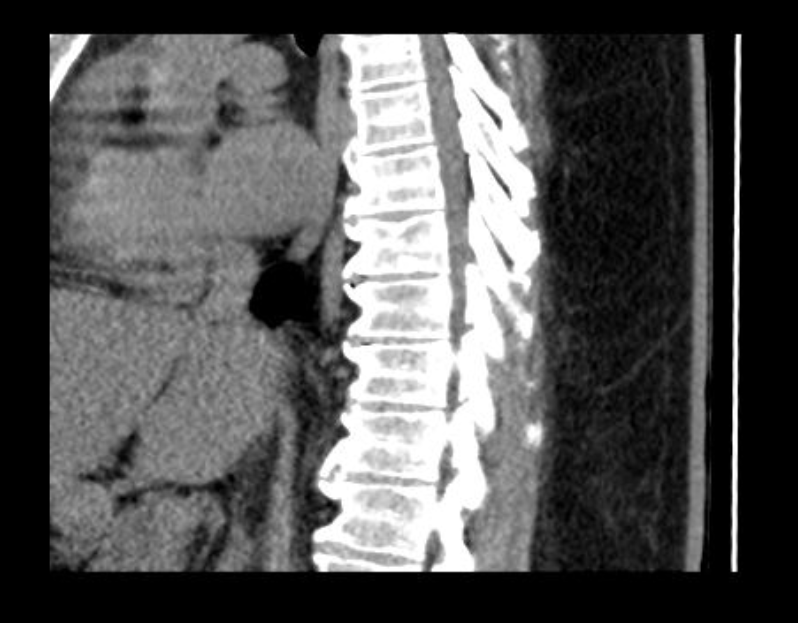

I’ve been diagnosed with Diffuse Idiopathic Skeletal Hyperostosis (DISH) and degenerative disc disease — both cause my spinal bones to stiffen and press on nerves. The pain runs across my lower back, hips, and legs, and sometimes even causes numbness around my lower back and thighs. I’ve tried to keep pushing through, but lately, even sleeping or sitting too long hurts.